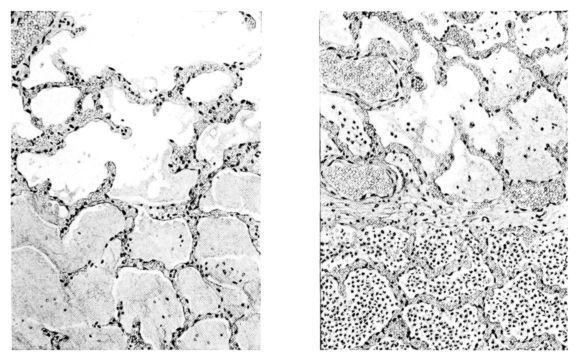

FIG. III. AUTOPSY NO. 90. DRAWING FROM A LESION OF THE TRACHEA (SOMEWHAT OLDER THAN THAT ILLUSTRATED IN FIGURE II). THE MUCOSA IS ENTIRELY LACKING. CONGESTION AND EDEMA ARE THE STRIKING FEATURES IN THE SUBMUCOSA. THE NECROTIZING PROCESS HAS EXTENDED INTO THE MUCUS GLANDS. THIS IS SHOWN IN THE LOWER PICTURE.

FIG. IV. AUTOPSY NO. 205. CONGESTION AND EDEMA OF THE SUBMUCOSA AND REGENERATION OF THE TRACHEAL EPITHELIUM.

Histological Picture.

The changes are less marked, perhaps, in the trachea than in its finer ramifications. The mucosa is constantly more or less destroyed and large areas, usually focal, are entirely devoid of their epithelial covering. This is replaced by a sparse exudate, composed largely of red blood cells, mucus, a small amount of fibrin, and nuclear fragments (Fig. II). It may dip into the submucosa for a short distance, but usually these indentures are associated with the ducts of the mucous glands into which the inflammatory reaction extends. A more striking feature than the exudate, however, is the edema and the congestion of the submucosa. The loose areolar tissue of the submucosa is spread widely apart, and throughout it distended blood vessels are very conspicuous. Occasionally such a vessel is broken and actual hemorrhage appears in the submucosa. Occasionally, too, the inflammation extends down the duct to the mucous gland itself, and here, also, aplastic inflammatory reaction is evident, inasmuch as the acini now stain intensely red with the cells undifferentiated from each other and specked here and there by broken remains of the dead nuclei (Fig. III). After the disease has continued for a short period, even at the end of five or six days, some regeneration of the epithelial lining may be seen (3) (Fig. IV). But despite this, the acute picture persists, and there goes on, side by side, an attempted repair characterized by epithelial regeneration and the same evidence of acute change. Since the lesion is essentially a superficial one, scars or contractures of any extent are not encountered in the trachea, even in examples of the disease that have ended fatally only after many weeks.[4]